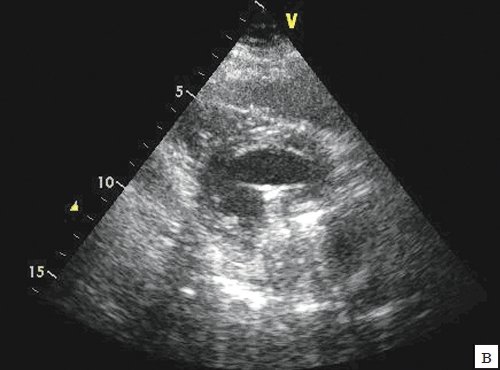

Наиболее близким к нативному является кровоток у биологических протезов: гибкие створки биопротеза в диастолу обеспечивают свободу просвета проходного отверстия клапана и создают гораздо меньшее препятствие для транспротезного кровотока. Кровоток через биологический протез носит преимущественно ламинарный характер, ориентированный по длинной оси ЛЖ к его верхушке (рис. 3).

а) Апикальный доступ.

б) Апикальный доступ, с увеличением.

в) По короткой оси.

г) С цветным картированием транспротезного потока.